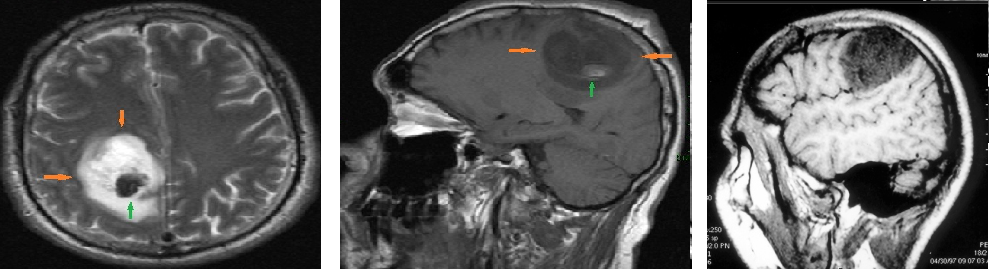

Ironicamente, apesar da maioria das premissas básicas da frenologia terem sido consideradas pseudociência, as leituras dos comportamentos e a sua relação com o crânio não foram. O princípio de que as funções específicas cerebrais estão localizadas em topografias determinadas é agora conhecimento comum demonstradas por técnicas modernas de imagem, como a ressonância magnética funcional (FMRI). Esta doutrina que possibilita a visualização precisa de uma determinada função quando ela está sendo realizada é chamada de localizacionismo cerebral.

Em 1861, já foi correlacionado por Broca o fenômeno clínico da afasia motora com o achado patológico de lesão específica da porção posterior do giro frontal inferior, constituindo base de estudos paleontológicos atuais dos crânios de hominídeos primitivos para determinar os formatos dos cérebros e a presença de um nó alargado na região de Broca provando assim a origem do uso de nossa linguagem verbal. Além disso, é também confirmado que as áreas do cérebro que são mais frequentemente utilizadas podem hipertrofiar-se, como por exemplo, o hipocampo direito dos taxistas de Londres. Esta é essencialmente a frenologia sob uma nova aparência.